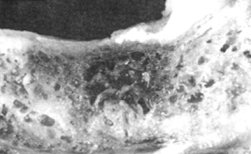

In this black-and-white photo, we see a cross-section of an autopsied jawbone, with a cavitation showing the necrotic dead bone tissue. This cavitation was caused by an extracted tooth.